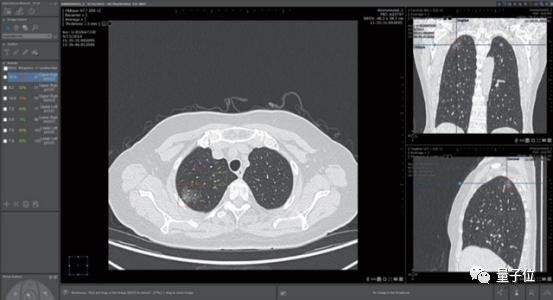

醫療影像輔助診斷是當時醫療AI公司扎堆投入的領域。這家公司最大的賣點肺結節診斷,則是紅海中的紅海。

一家醫院接入4、5家AI肺結節診斷產品成了司空見慣,曾有影像醫師笑稱:

中國人的肺結節都不夠用了。